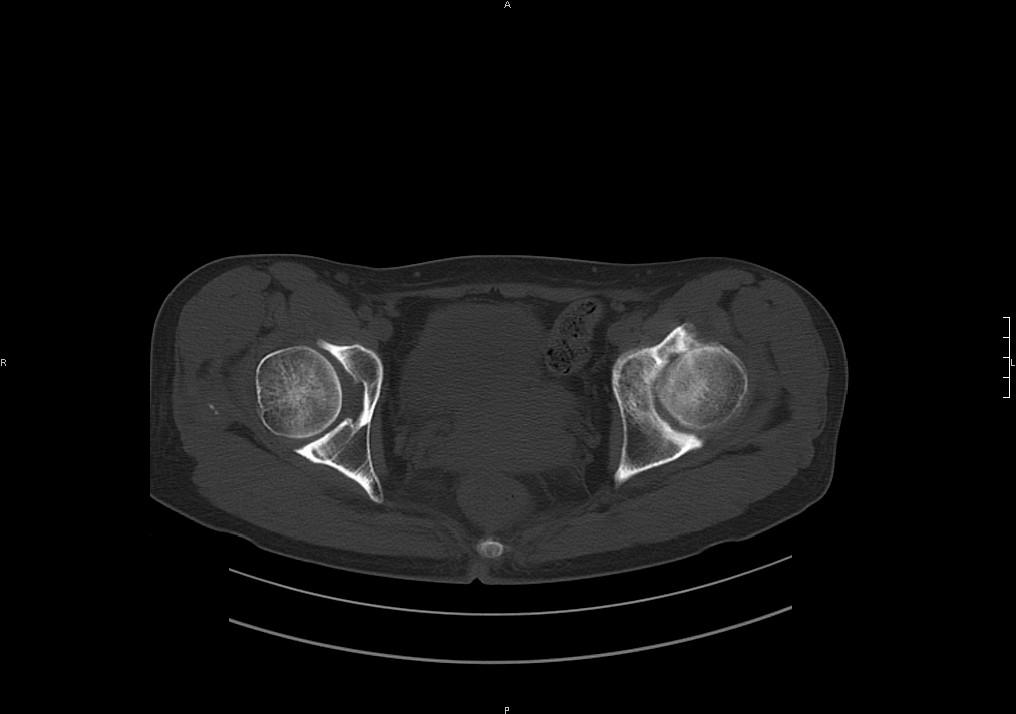

标题: CT19780左髋关节疼痛伴跛行1年,加重1个月。无菌性坏死? [打印本页]

标题: CT19780左髋关节疼痛伴跛行1年,加重1个月。无菌性坏死?

没报年龄,但髋臼有骨质增生, 考虑退行性变,坏死不明显。

左髋关节内内可见关节鼠及滑囊积液.

考虑为滑膜骨软骨瘤病.

滑膜增厚钙化,关节鼠及滑囊积液,髋臼增生。考虑骨性关节病

髋臼平浅,股骨头覆盖率减小,考虑双侧髋关节发育不良伴退行性变。

考虑左髋关节退行性骨关节病;建议必要时行mri检查排除左侧股骨头缺血性坏死。

股骨颈陈旧性骨折

髋关节退行性骨关节病